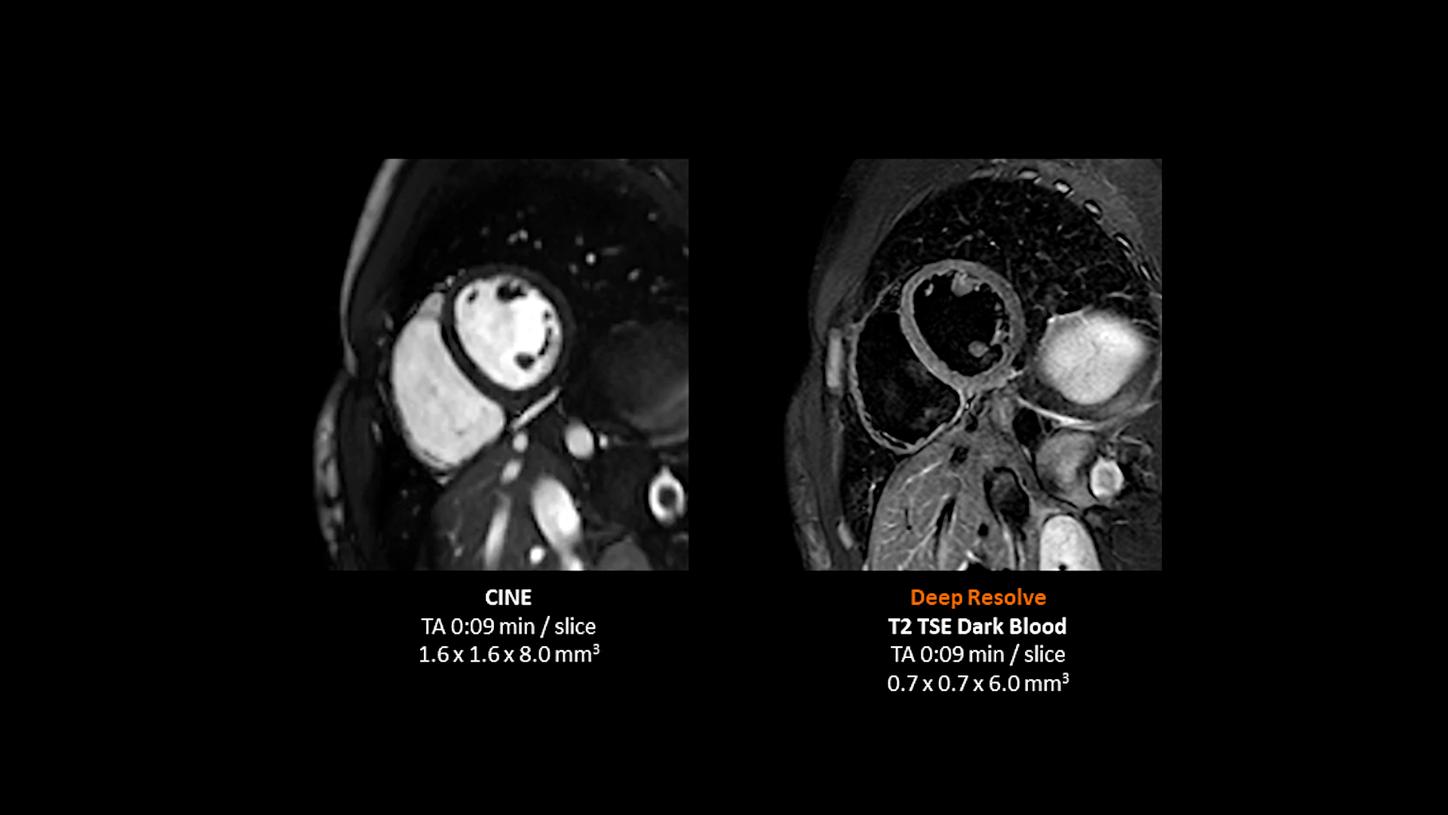

Deep Resolve will be at the forefront of the revolution in MRI acceleration. Deep Resolve will enable our fastest MRI, with images that will have extraordinary clarity, higher clinical productivity, and an even better patient experience. This transformational effect of Deep Resolve is now planned to expand to 3D5, unlocking a new dimension in MRI image resolution and speed.